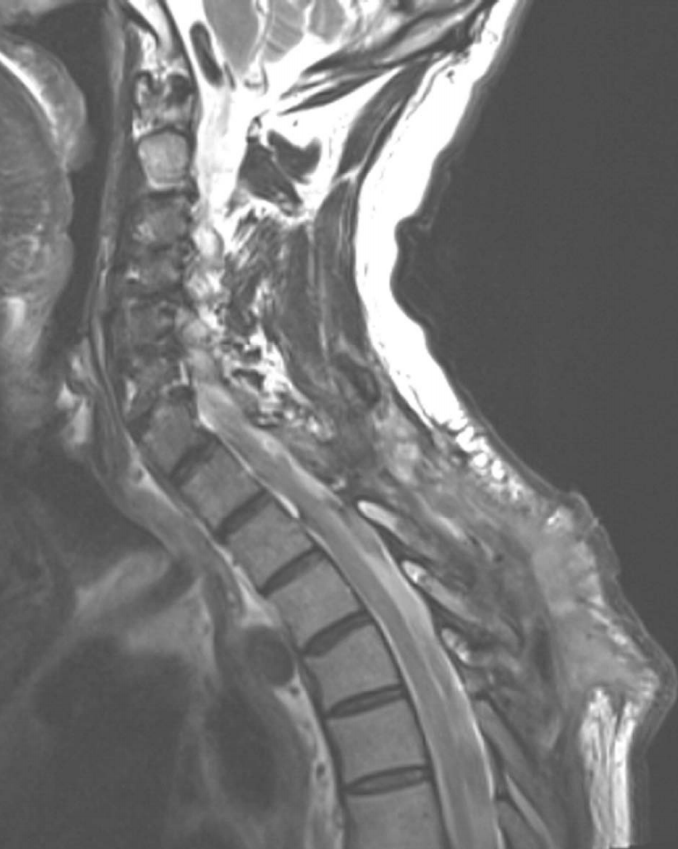

科学探讨:如何定义和诊断脊髓空洞症?

本文根据神经放射学及临床检查,提出脊髓空洞症的定义及诊断方法...